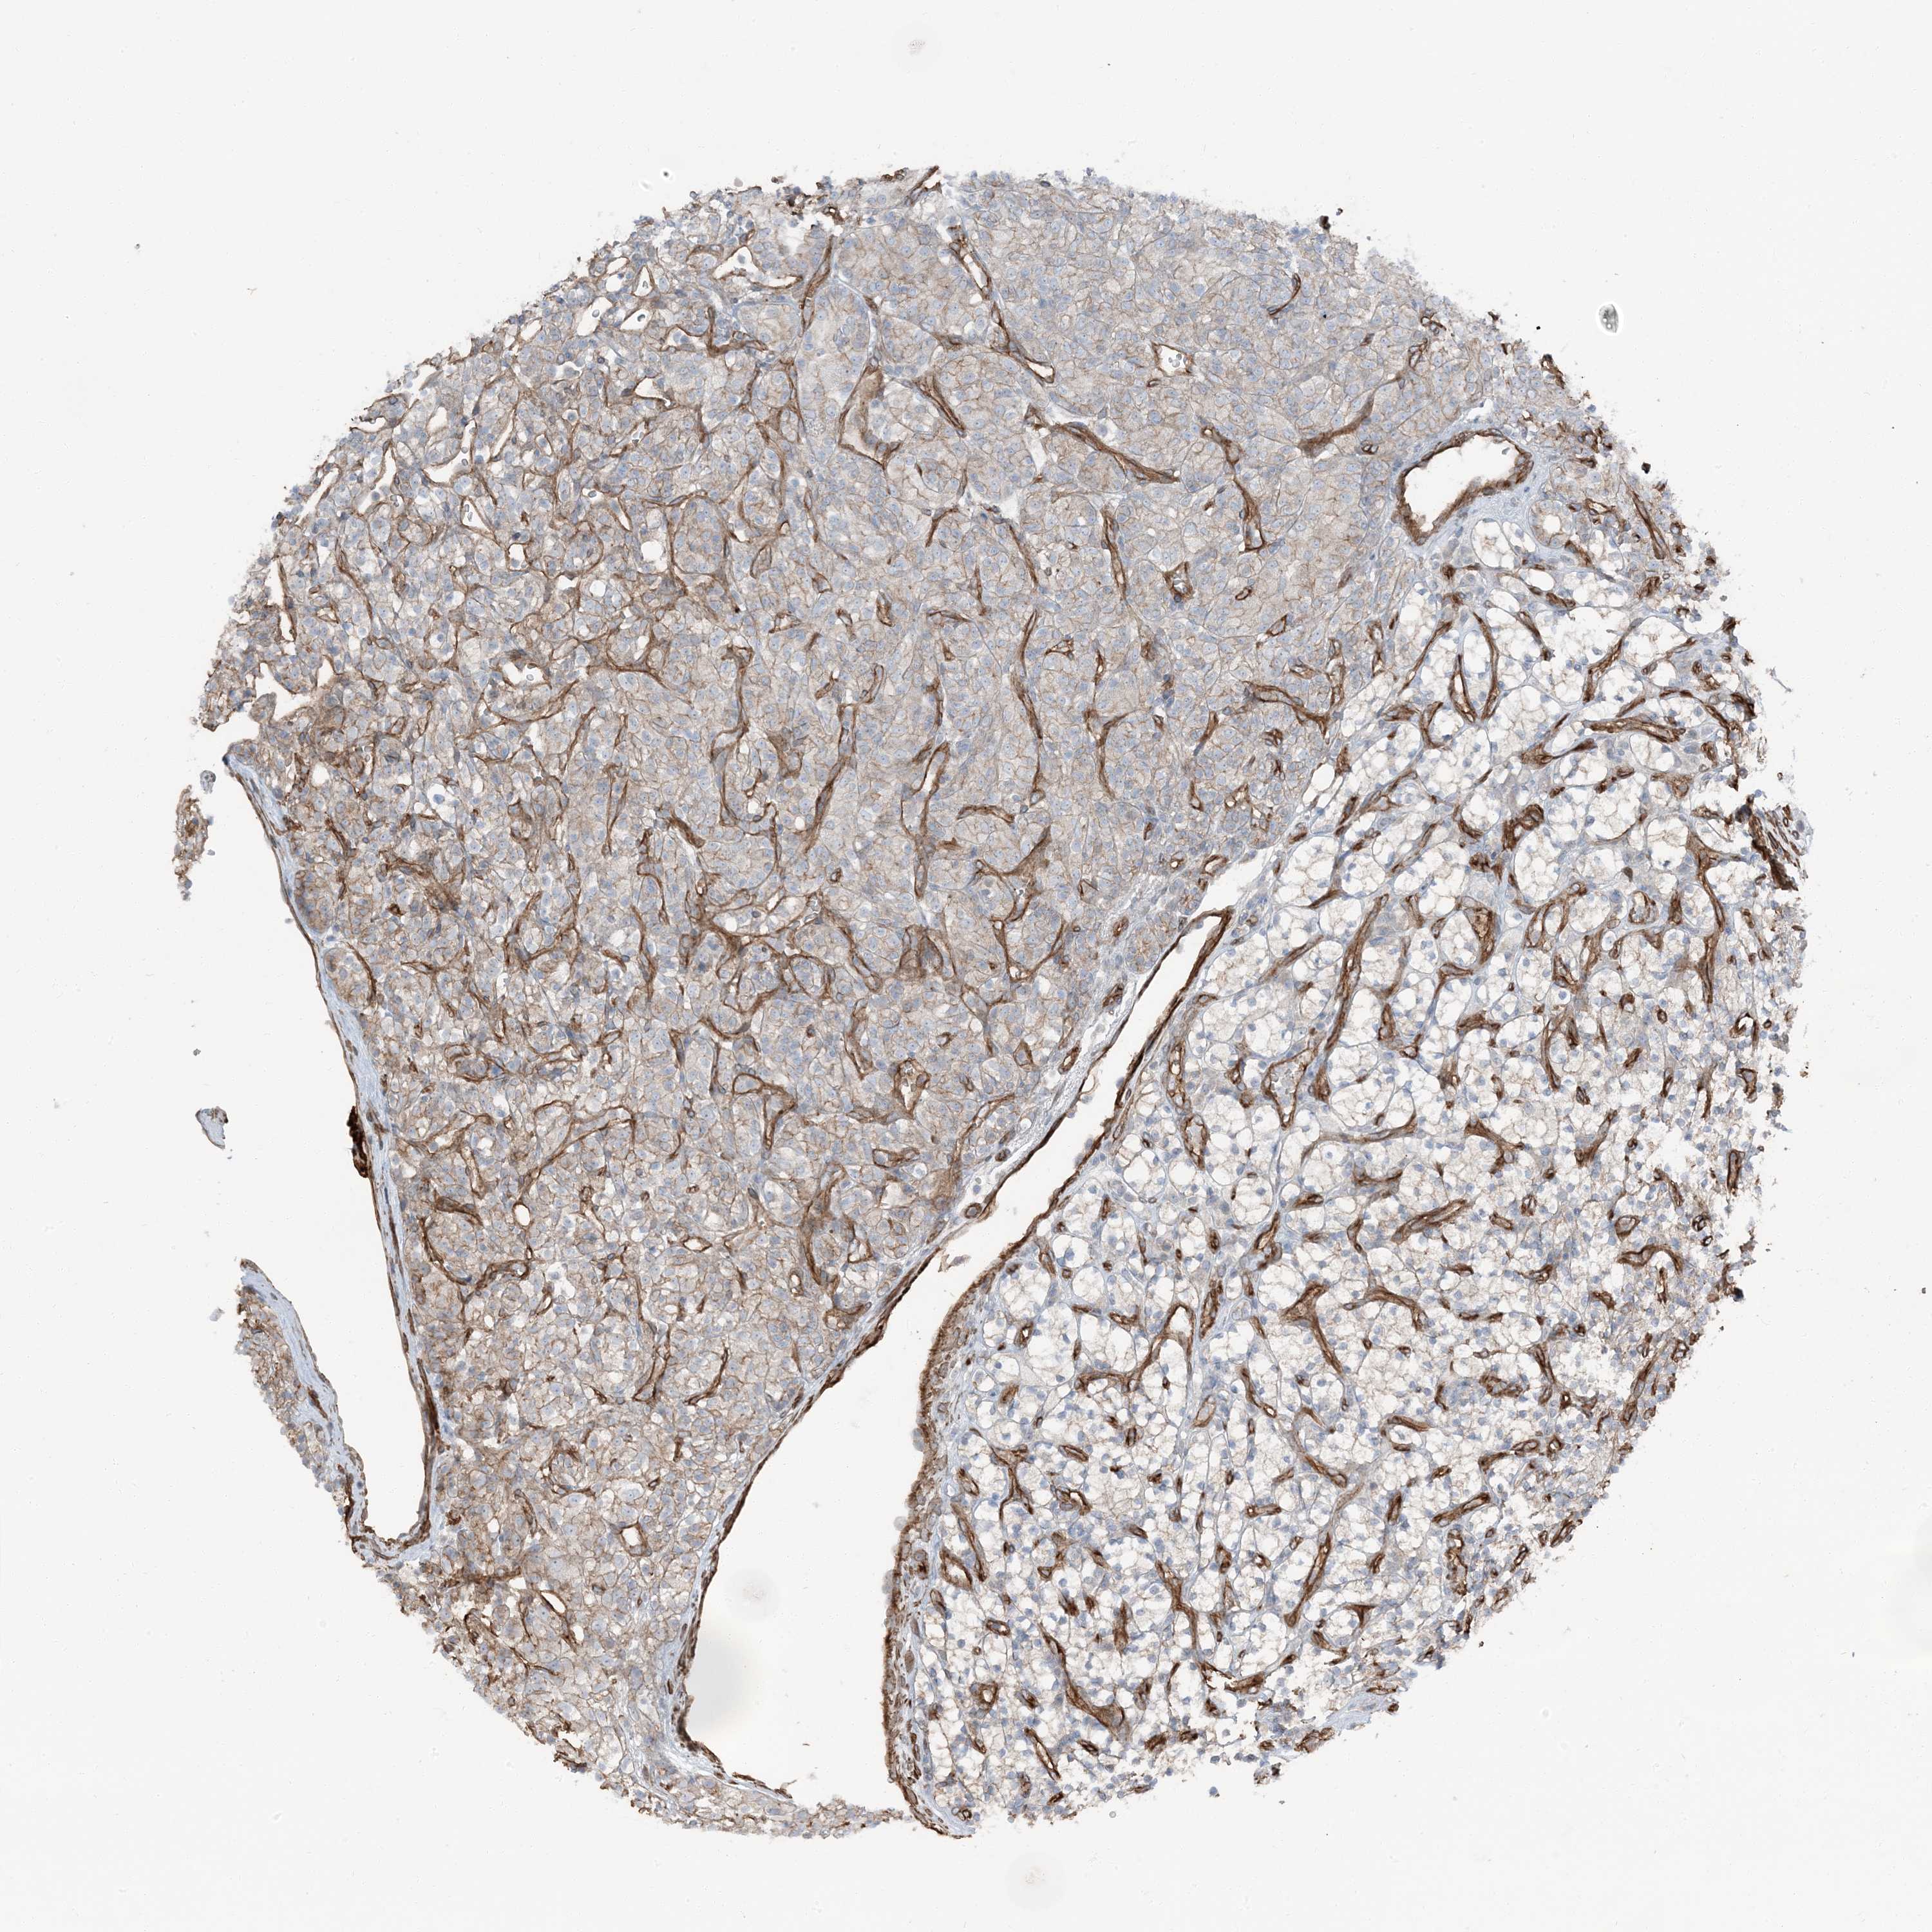

KIDNEY RENAL CLEAR CELL CARCINOMA (VALIDATION) - Interactive survival scatter ploti

The Survival Scatter plot shows the clinical status (i.e. dead or alive) for all individuals in the patient cohort, based on the same data that underlies the corresponding Kaplan-Meier plots. Patients that are alive at last time for follow-up are shown in blue and patients who have died during the study are shown in red.

The x-axis shows the expression levels (FPKM) of the investigated gene in the tumor tissue at the time of diagnosis. The y-axis shows the follow-up time after diagnosis (years). Both axes are complimented with kernel density curves demonstrating the data density over the axes. The top density plot shows the expression levels (FPKM) distribution among dead (red) and alive patients (blue). The right density plot shows the data density of the survived years of dead patients with high and low expression levels respectively, stratified using the cutoff indicated by the vertical dashed line through the Survival Scatter plot. This cutoff is automatically defined based on the FPKM cutoff that minimizes the p-score. The cutoff can be changed by dragging the vertical line or by entering a cutoff value in the square labeled "Current cut-off".

Under the Survival Scatter plot the p-score landscape (black curve; left axis) is shown together with dead median separation (red curve; right axis). Dead median separation is the difference in median mRNA expression between patients who have died with high and low expression, respectively. It is calculated as follows: median FPKM expression of dead patients with high expression - median FPKM expression of dead patients with low expression. This is intended to aid the user in visually exploring custom cutoffs and the associated p-scores and dead median separation.

Individual patient data is displayed and can be filtered by clicking on one or more of the category buttons on the top of the page. Categories describing expression level and patient information include: high, low, alive, dead, female, male and tumor stages. The scale of the x-axis can be toggled between linear and log-scale by clicking on the "x log" button. Mouse-over function shows TCGA ID, patient information and mRNA expression (FPKM) for each patient.

& Survival analysisi

Kaplan-Meier plots summarize results from analysis of correlation between mRNA expression level and patient survival. Patients were divided based on level of expression into one of the two groups "low" (under cut off) or "high" (over cut off). X-axis shows time for survival (years) and y-axis shows the probability of survival, where 1.0 corresponds to 100 percent.

ZFP90 is not prognostic in Kidney Renal Clear Cell Carcinoma (validation)

Best expression cut offi

Based on the FPKM value of each gene, patients were classified into two groups and association between prognosis (survival) and gene expression (FPKM) was examined. The best expression cut-off refers the FPKM value that yields maximal difference with regard to survival between the two groups at the lowest log-rank P-value. Best expression cut-off was selected based on survival analysis .

When clicking on this number, the vertical dashed line indicating cut-off, the interactive survival plot, and the Kaplan-Meier curve will be adjusted to show results based on the best expression cut-off.

: 16.98

P scorei

Log-rank P value for Kaplan-Meier plot showing results from analysis of correlation between mRNA expression level and patient survival.

N/A

TCGA RNA samplesi

RNA-seq data is reported as average FPKM (number Fragments Per Kilobase of exon per Million reads), generated by the The Cancer Genome Atlas (TCGA) .

Normal distribution across the dataset is visualized with box plots, shown as median and 25th and 75th percentiles. Points are displayed as outliers if they are above or below 1.5 times the interquartile range. FPKM values of the individual samples are presented next to the box plot.

Average pTPM 14.4

Number of samples 100